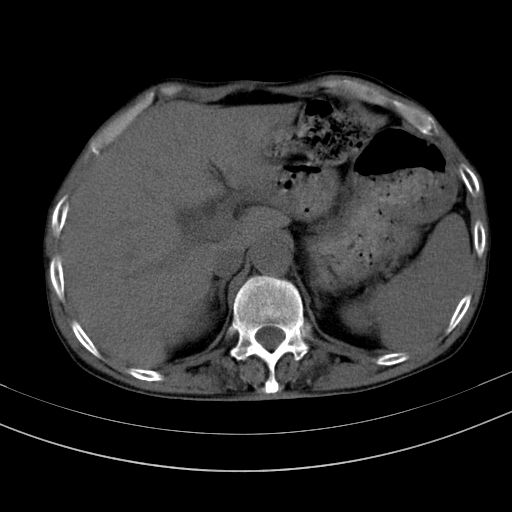

以下是引用dyqct在2010-1-9 17:56:00的发言:[br]考虑:1.双肾囊肿,左肾积水结石、旋转不良。[br] 2.右侧腹直肌血肿或纤维瘤。[br]肠道准备不好。做个增强。